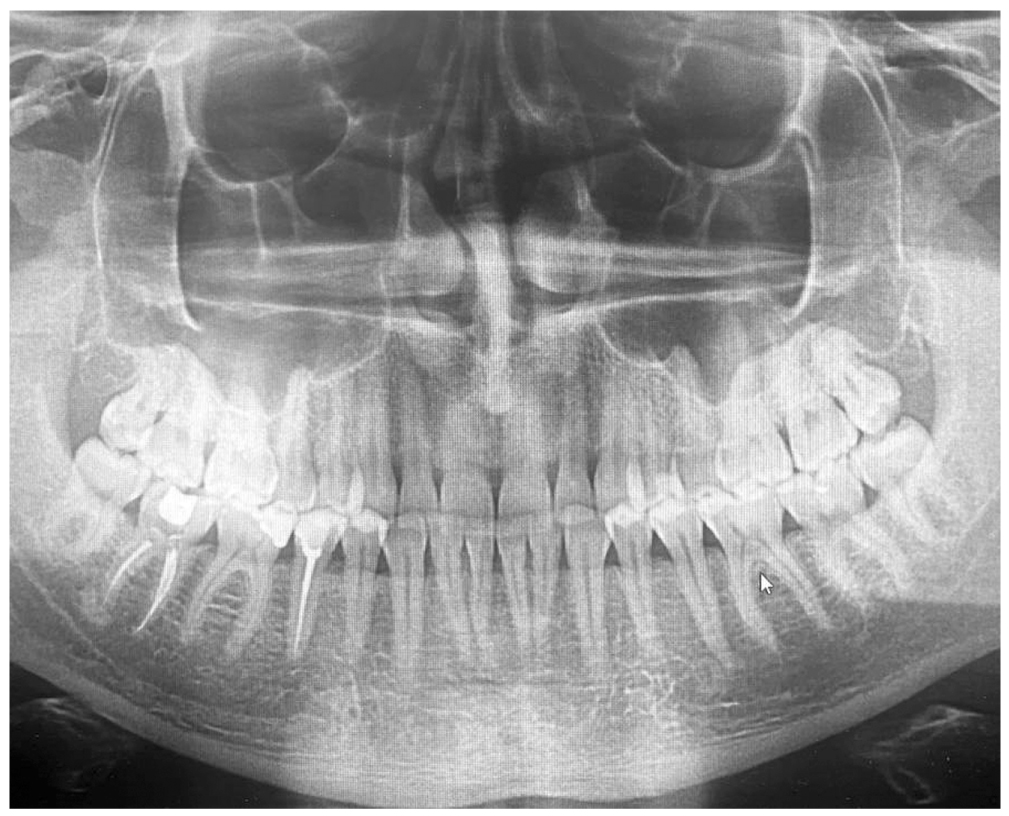

Three disease stages are known — mild, moderate and severe. The mild degree of severity is characterized by the presence of swelling, cyanotic and bleeding mucosa of the gingival margin, 1st degree loosening of teeth and by the presence of a periodontal recess up to 4 mm deep. The radiology images in cases of mild disease show dilation of periodontal fissure, loss of integrity in the cortical plate, resorption of the alveolar bone walls by 1/3 of the dental root length. In cases of moderate severity of chronic generalized periodontitis, the findings include an increase in the depth of periodontal recess up to 6 mm, pathological loosening of teeth (2nd degree) and exposition of the dental roots. The orthopantomograms from the patients with 2nd degree show resorption of alveolar bone walls, reaching up to 1/2 of the length of the dental root and showing signs of destruction in the cortical plate. The severe chronic generalized periodontitis is characterized by an increase in the pathological loosening of teeth (up to degree II or III), by dislocation of teeth, by the presence of periodontal recesses with a depth of more than 6 mm and with the presence of purulent exudate, by significant traumatic occlusion and exposition of the roots. Upon radiology examination, the findings include resorption of alveolar bone walls to a distance of more than 1/2 of the dental root length with the presence of pathological bone pockets.

In patients with mild degree chronic generalized periodontitis (Group 1), the orthopantomogram was showing a dilation of the periodontal fissure, loss of integrity in the cortical plate, resorption of alveolar bone walls by 1/3–1/4 of the length of dental root (Fig. 1), with this being said, the mean value of genomic equivalent per 1 ml of biological sample (GE) for T. forsythia was 5.0±1.03, which is 1.5 times more than the values in the control group (p=0.012) (Fig. 2).

Fig. 1. Orthopantomogram — patient K. aged 44 years old: chronic generalized periodontitis of mild severity degree.